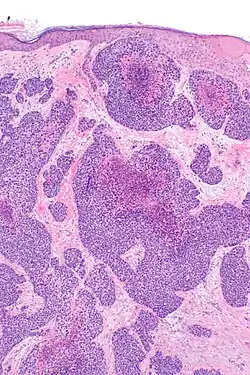

Histopathology

The microscopic histopathology of benign poroma tumors stained with hematoxylin and eosin dyes consists of poroid cells (i.e. small, round cells with oval nuclei and little cytoplasm) admixed with cuticular cells (i.e. epithelium-like cells) with centrally placed nuclei and abundant eosinophilic (i.e. colored pink or red due to uptake of the eosin stain) cytoplasm.[14] Porocarcinomas differ from poromas by their content of cells that are more irregular in size and contain misshaped nuclei[14] that often have conspicuous nucleoli.[15] Unlike the tumor cells in poromas, PCA tumor cells often appear to invade nearby normal tissues.[1] are rapidly proliferating as evidenced by their increased mitotic activity, and may have differentiated (this process is termed metaplasia) to appear as squamous cells, clear cells, mucous cells, or spindle cells.[11] PCA tissues may contain areas of necrosis (i.e. dead cells).[16]